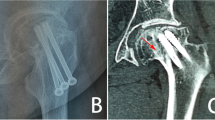

Proximal femoral fractures, see Figs. 1a and 2, are one of the most commonly observed fractures. Annually, approximately around 10,000 to 15,000 of these accidents occur in the Czech Republic; see [1]. The number reaches up to 900,000 cases in Europe every year. For more information see [1, 6, 11,12,13,14].

The treatment of proximal femoral fractures, see Fig. 2, is associated, apart from therapeutic problems, also with social and economic issues, taking into consideration the long period of treatment. In young patients, this type of fracture occurs especially due to high-energy mechanisms, such as traffic accidents, falls from height, and also adrenaline sports. In older individuals, the fractures are most frequently caused by low-energy injuries, e.g. falls at home. The first (and less frequently observed) group of fractures comprises fractures of the femoral head, which most frequently occur during dislocation of the hip joint.

The type of osteosynthesis in intracapsular fractures depends mainly on the age of the patients. In young individuals, procedures which preserve the femoral head are usually chosen; this is based on the assumption that a few patients may require a joint replacement at a later stage, following the development of avascular necrosis (AVN). There is a choice between osteosynthesis performed with lag cancellous screws and the DHS procedure, with placement of antirotation screws. Identical methods are also suitable for nondislocated and minimally dislocated fractures in patients of higher age; see Fig. 3.

Osteosynthesis with lag spongious screws is also clearly indicated in cases of proximal femur fractures in children, in combination with osteosynthesis using Kirschner wires introduced through the epiphyseal growth zone; see Fig. 4.

Child’s intracapsular femoral fracture a anteroposterior X-ray, b Osteosynthesis with two lag spongious screws and two Kirschner wires through the epiphyseal zone (anteroposterior X-ray), c Osteosynthesis with two lag spongious screws and two Kirschner wires through the epiphyseal zone (lateral X-ray)

Osteosynthesis of femoral neck fractures with lag spongious screws is usually performed on children and young patients with intracapsular fractures, but also on patients of a higher age with nondislocated intracapsular fractures; see Fig. 5. The use of lag spongious screws belongs among the mini-invasive techniques; the placement of two or more screws provides rotational stability. Length stability is provided by the placement of the screw tips into the subchondral bone and by supporting the screw head with an underlay, see Fig. 6.